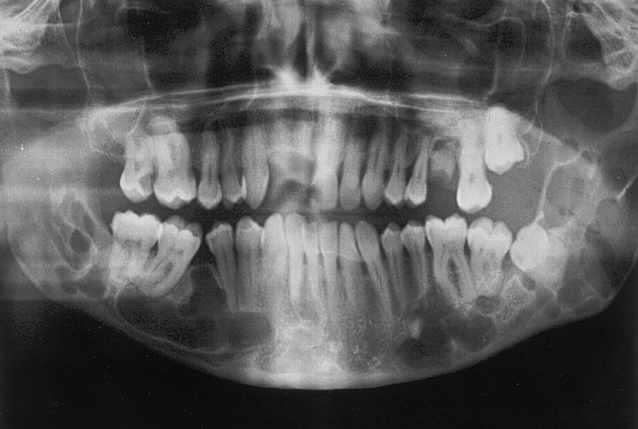

Pacientul I.T. s-a prezentat la cabinet cu dureri și sângerări la partea anterioară a maxilarului. După prima consultație s-a diagnosticat cu chist la nivelul osului maxilar.

Chisturile oaselor maxilare reprezinta cauza ce mai frecventa a deformarilor osoase cronice de la nivelul viscerocraniului. Aceste entitati clinice si histopatologice se dezvolta in special la nivelul oaselor maxilare, localizarile la nivelul altor oase ale corpului fiind relativ rare. In plus, o serie de leziuni chsitice  non-odontogene, care afecteaza scheletul in general se pot regasi uneori si la nivelul oaselor maxilare. Localizarea cu predilectie la nivelul maxilarelor se explica prin prezenta a numeroase resturi epiteliale odontogene, provenite din procesul de dezvoltare a dintelui (odontogeneza) si restante in oasele maxilare.

Aspectul tipic pentru o forma de mici dimensiuni este de radiotransparenta uniloculara, care inconjoara coroana unui dinte inclus sau semiinclus si care se ataseaza la coletul dintelui. In evolutie, atasarea la coletul dintelui este relativa pe imaginea radiografica.

Radiotransparenta este bine delimitata, cu contur net, adeseori discret radioopac; in cazul in care a fost suprainfectat, limitele chistului par mai putin nete. Trebuie avut in vedere faptul ca exista o serie de variatiuni ale acestui aspect radiografic.

Varianta cu extensie laterala este prezenta in cazul unui molar de minte inferior semiinclus, in care radiotransparenta intereseaza doar portiunea distala a dintelui, spre ramul mandibular.

Varianta cu extensie vestibulara apare in contextul unui molar de minte inferior semiinclus, incat imaginea radiografica este de radiotransparenta uniloculara suprapusa peste bifurcatia radacinilor acestui dinte. Aceasta varianta a fost denumita si chist paradentar sau  chist vestibular de bifurcatie, considerat de unii autori ca entitate clinica separata, cu localizare la nivelul primului molar sau molarului trei inferior.

Varianta „circumferentiala” se prezinta ca o radiotransparenta care se extinde spre apical, nerespectand jonctiunea amelo-dentinara a coletului dentar, sau poate chiar circumscrie radiografic dintele. In cazul chisturilor foliculare de mari dimensiuni, aspectul poate fi aparent multilocular, dar acesta se datoreaza unor trabecule osoase restante, suprapuse peste radiotransparenta chistului.